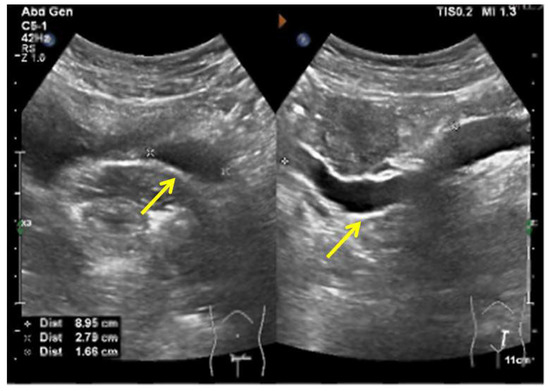

A woman of 33 years old was advised to undergo a hysteroscopy before receiving assisted reproductive technologies. She received a hysteroscopic uterine septum resection at age 27. Her right fallopian tube was removed due to two ectopic pregnancies. A pelvic examination showed an oblique septum extending 3 cm from the left fornix of the vagina to the hymen border. The pelvic ultrasound demonstrated an ectopic ureter or ureterovaginal fistula (Figure 10). An MRI and CTU detected left renal agenesis and a left dilated ureter with an ectopic opening. Following vaginal septum excision, a double cervix with a dysplastic left cervix was found. Given that the left ectopic ureter was asymptomatic, this ectopic ureter was not surgically removed.

Figure 10.

The pelvic ultrasound demonstrated that a sausage-shaped ectopic ureter (yellow arrow) was found behind the uterus and bladder.